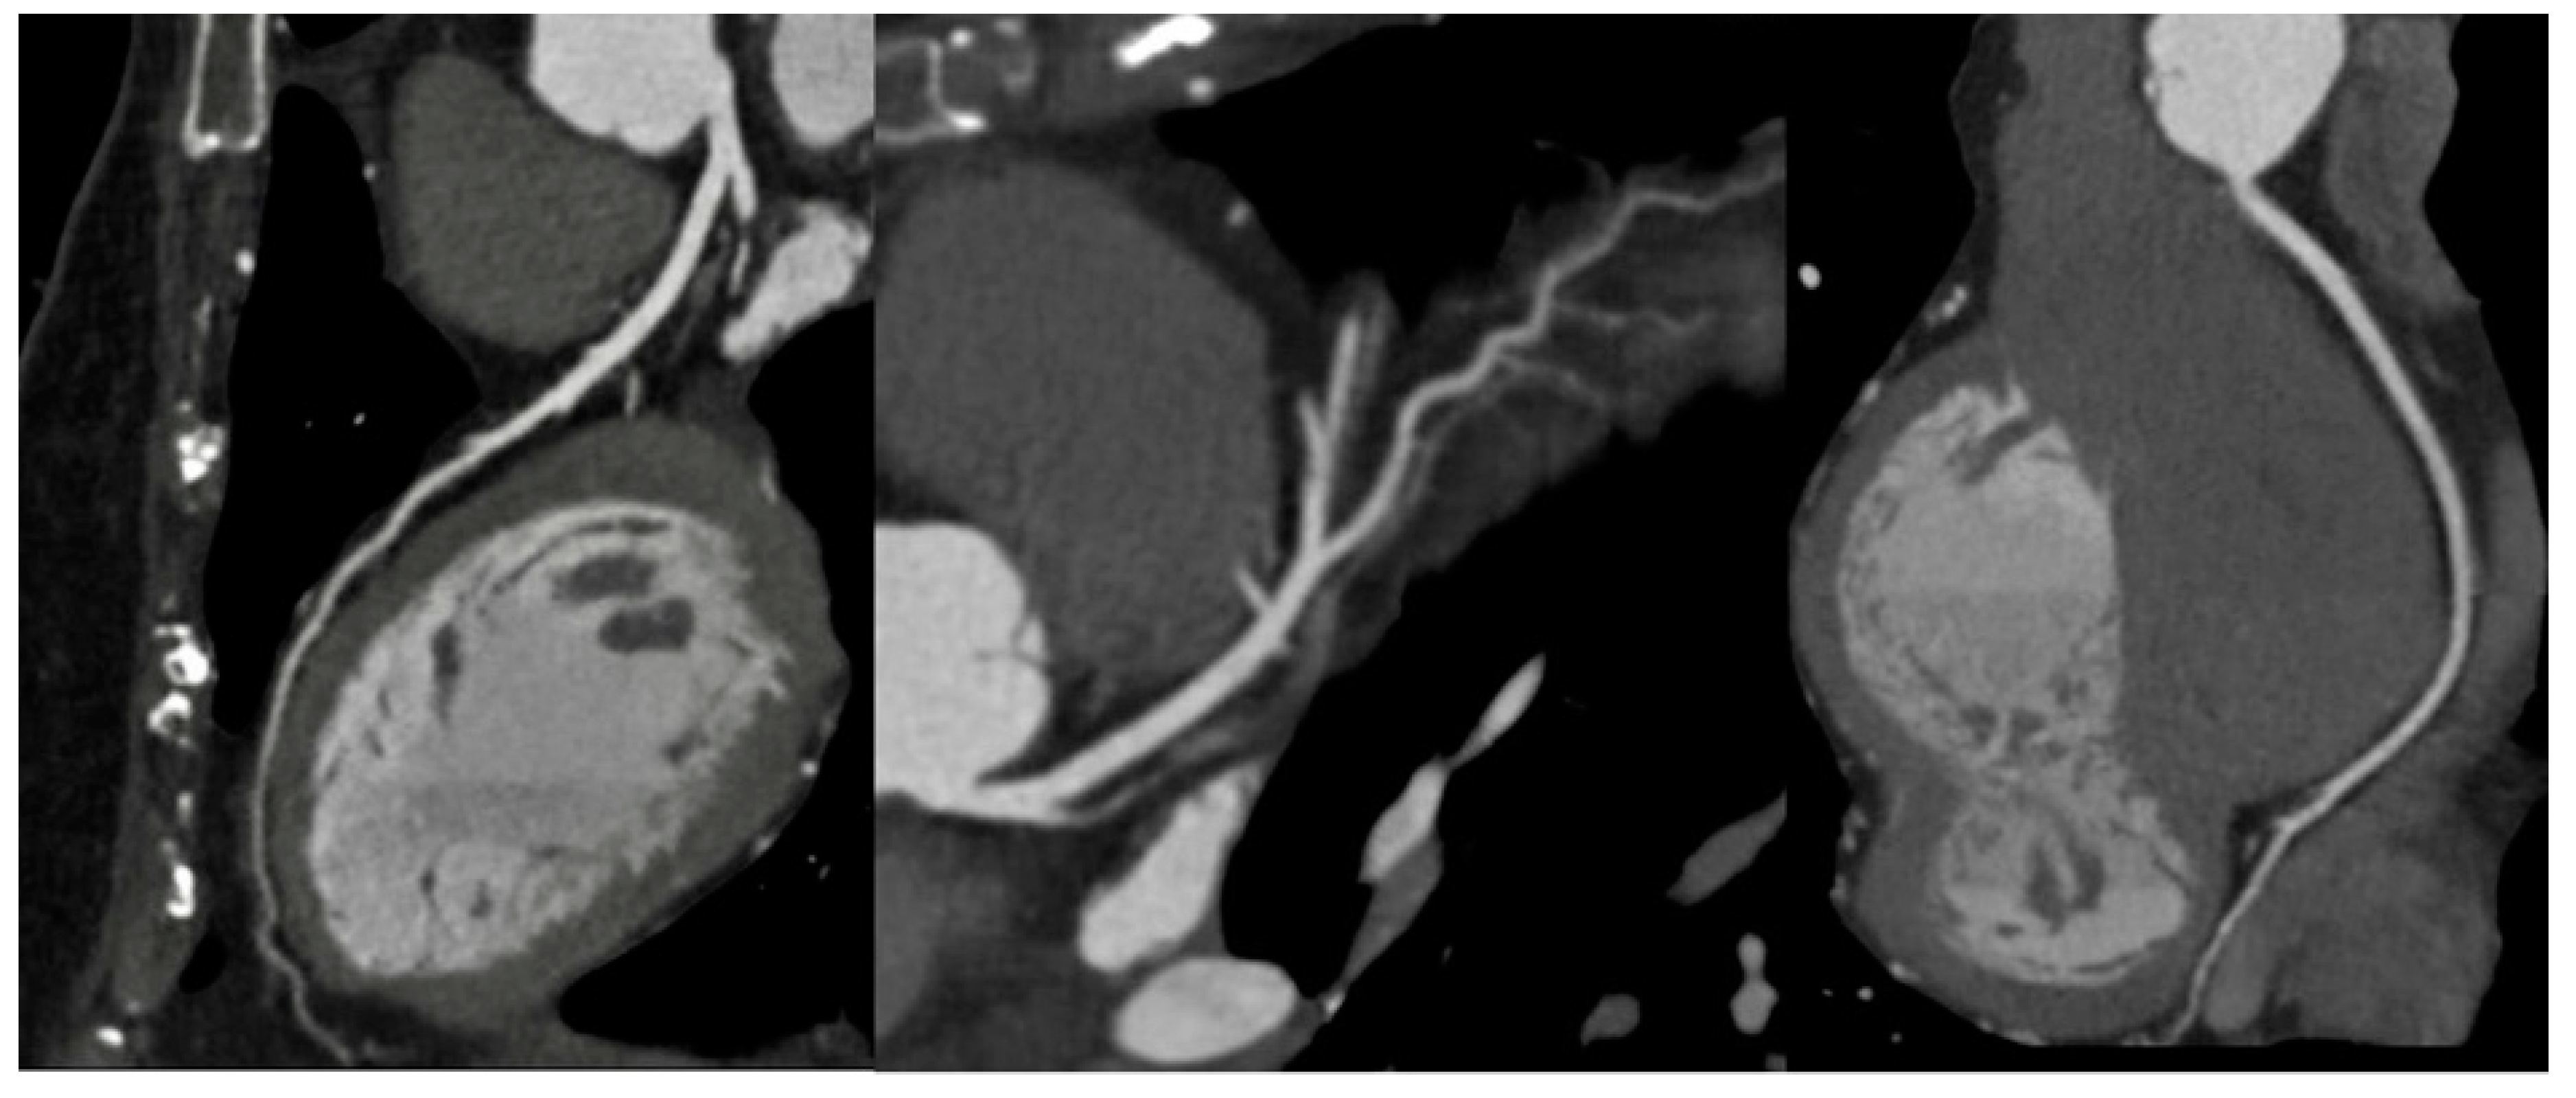

In Italy, CTA is the technique routinely employed in aortic imaging. Nowadays, multidetector row CT (MDCT) scans are highly efficient, widely available, and are highly sensitive and specific in diagnosing acute aortic syndromes (AAS) such as dissections, intramural hematomas, penetrating ulcers. Moreover, MDCT provides detailed insights into the vessel’s thickness and composition, allowing the evaluation of vasculitis and, in the emergency setting, it has been more and more employed to localize the sources of gastrointestinal bleeding(Geffroy et al., 2011). Maximum intensity projection (MIP) reconstruction provides global assessment and rapid detection of vascular stenosis and occlusion(Hyde et al., 2007). Pre-procedural MDCT is crucial for percutaneous interventions, such as transcatheter-aortic-valve-replacement and transcatheter -mitral-valve-replacement. While transthoracic echocardiography is often employed in monitoring post-procedure results with a limited acoustic window, potential complications are generally investigated by CT scans(Francone et al., 2020). In routine surgical scenarios, post-processing techniques, such as multiplanar reformats and segmented volume-rendered (VR) reconstructions, have greatly improved the assessment of vascular anatomy and they are generally requested by cardiac surgeons [Figure 5].

New CT systems, such as dual-energy CT (DECT) and photon-counting CT (PCCT) have been recently introduced. DECT surpasses conventional CT scans by attenuation measurements from different energy spectra, quantifying material composition (So et al., 2012). This novel method facilitates the separation and quantification of iodine concentrations, enabling a better assessment of tissue perfusion,and it is particularly interesting in the study of acute aortic syndrome, where extravasation, intramural hematoma, and endoleak are challenging to accurately image by conventional CT(Jacobsen et al., 2020). PCCT offers complete spectral multi-energy data information, with small detector pixel design, and better spatial resolution facilitating the assessment of iodine density and the quantification of diverse virtual monoenergetic images (Leng et al., 2019). PCCT guarantees that patients reduce noise and artifacts along with minimal radiation doses for evaluating disease processes and optimal dose efficiency. This ensures a superior CT angiographic examination and enhances patient safety (Counseller & Aboelkassem, 2023). By intravenous administration of two contrast agents, PCCT can capture endoleak dynamics and discriminate endoleaks from intra-aneurysmatic calcifications in a single scan reducing the radiation exposure. It also has the potential to improve the visualization of the stent deployment (Meloni, Frijia, et al., 2023).

The clinical use of 4D-flow MRI has only recently become available. With ECG-gated time-resolved acquisition, a 3D image of blood flow in all three spatial directions can now be captured, allowing visualization of blood flow in the vessels extending from the brain to the lower extremities(Dyverfeldt et al., 2015). Additionally, assessments of wall shear stress, pulse-wave velocity, and pressure gradients can be performed alongside blood flow estimation. MRA combined with 4D flow MRI offers an advantage over dynamic CTA in imaging the whole aorta with no radiation burden; however, its sensitivity in detecting endoleaks has yet to be determined, and further large-scale studies are necessary to determine its optimal use(Qin et al., 2023).